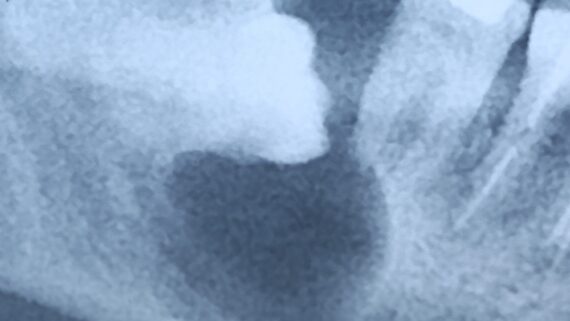

сделать операции синуслифтинга с двух сторон:

на фотографии, кстати, редкий случай многокамерной пазухи, с перегородкой посередине. В подобных ситуациях синуслифтинг, хоть и получается сложнее, но все равно осуществим.